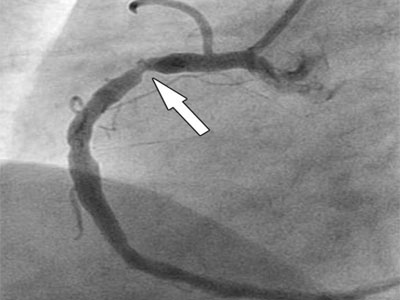

Страдаете от периодических болей в области сердца, не знаете, к какому специалисту обратиться? Коронарография в Воронеже